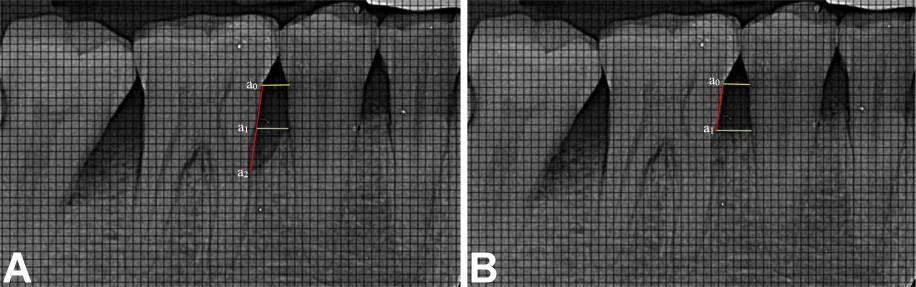

Radiographic bone fill (RBF) was recorded at baseline, and at 6 and 9 months. The models were fabricated from alginate impressions, on which customized X-ray positioning stents were prepared. L-shaped self-curing acrylic resin bite blocks were fabricated on the occlusal surface in the premolar–molar region to retain the plastic film holder using the long cone paralleling technique. The radiographic stent was then evaluated in the patient’s mouth for adequate retention and stability (Figure 2). Dentsply Rinn XCP-DS FIT (Dentsply Sirona, Charlotte, USA) with a posterior aiming ring and a radiographic grid of 1 mm × 1 mm was used for assessment. The exposure parameters were maintained at 75 kVp, 6 mA and 0.8 s. The same voltage was used for taking the radiographs, and the contrast of the radiograph was set to a similar numerical value in SOPRO Imaging software (http://www.soprotechnicalsupport.com) at baseline and follow-up. Geometric errors were reduced by stent fabrication and the use of the long cone extension technique for both baseline and follow-up radiographs. The amount of bone formed was assessed by comparing the baseline and 9-month radiographs and drawing 2 horizontal lines at the cementoenamel junction (CEJ) and at the alveolar crest, respectively, using the adjacent tooth as a reference (Figure 3, Figure 4). Radiographic bone fill was measured from the CEJ to the base of the defect using SOPRO Imaging software.